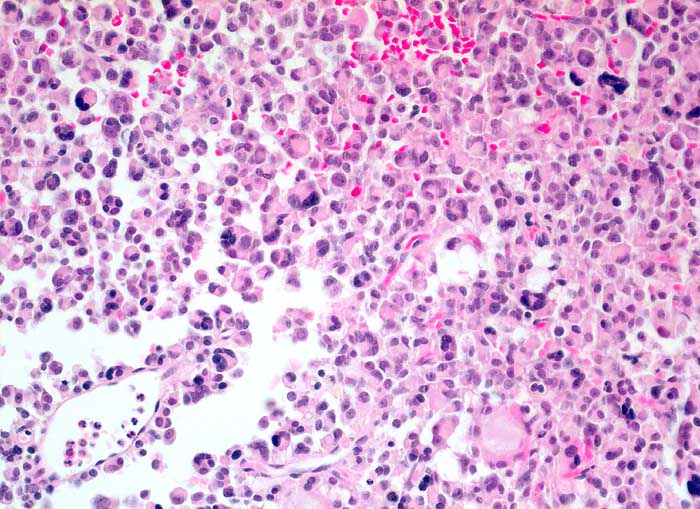

chromophobes Hypophysenadenom

Diffus wachsendes Hypophysenadenom mit zahlreichen mehrkernigen Zellen

Über 50% der Adenomzellen zeigen eine Expression für das Wachstumshormon. Lediglich Einzelzellen positiv für den Marker gegen Prolactin. Die übrigen angewandten Marker vollständig negativ. Der MIB-1-Proliferationsindex liegt deutlich unter 1%

Hypophysenadenom, Vd. a. atypische Akromegalie.

Histologie

200